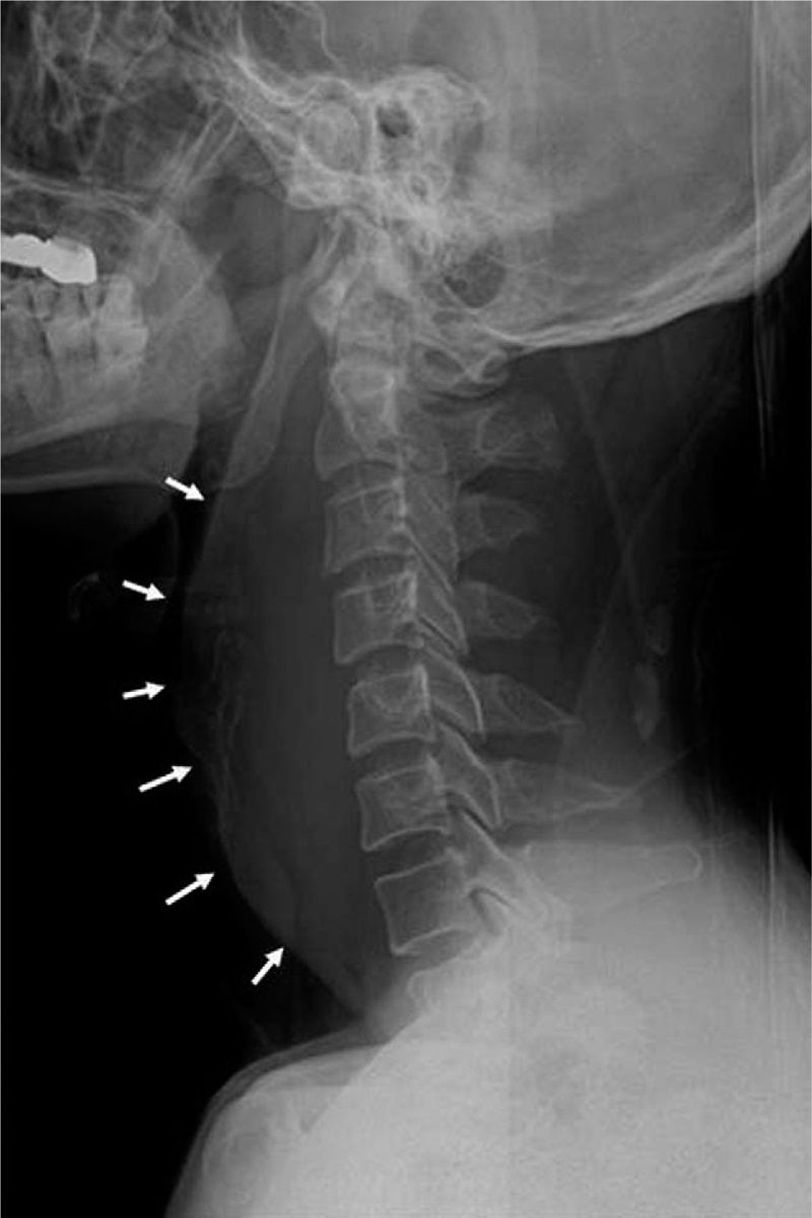

The biggest challenge faced by ER doctors and trauma surgeons is to identify all the potential injuries, both visible and concealed, and ensuring timely appropriate management in order to reduce morbidity and mortality. According to available literature, 1.3% to 39% of injuries may go unnoticed due to inadequate investigations in trauma patients. One such insidious injury is development of retropharyngeal hematoma as a result of major cervical trauma; however, a report described an anomalous case of retropharyngeal hematoma associated with minor blunt trauma. A 49-year-old gentleman was presented with history of road traffic accident which resulted in hyperextension of neck with no other visible injuries. The patient visited ER due to mild respiratory distress. Preliminary investigations were conducted; however, patient was discharged due to insignificant findings with clear instructions to visit ER if symptoms worsen. Patient presented 2 hours after discharge with dyspnea. Physical examination was unremarkable and vital signs were normal. Patient was intubated secondary to worsening dyspnea. Radiological investigations divulged an intense retropharyngeal hematoma. Neck exploration was done for hemorrhage control and removal of hematoma. Patient was discharged with no complications. Retropharyngeal hematoma is extremely hazardous if not identified earlier. Literature suggests frequent vigilant monitoring of minor trauma patients in order to timely identify potential life-threatening condition, several hours after trauma. Reference: Retropharyngeal hematoma secondary to cervical hyperextension in a minor collision trauma presenting with dyspnoea https://journals.lww.com/md-journal/subjects/Critical%20Care%20and%20Emergency%20Medicine/Fulltext/2020/07310/Retropharyngeal_hematoma_secondary_to_cervical.129.aspx (Image taken from: https://journals.lww.com/md-journal/subjects/Critical%20Care%20and%20Emergency%20Medicine/Fulltext/2020/07310/Retropharyngeal_hematoma_secondary_to_cervical.129.aspx)